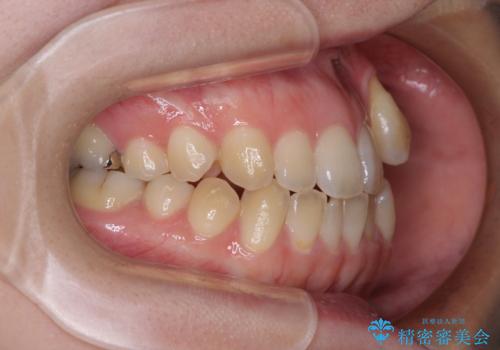

急速拡大装置 狭い上顎骨を拡大してワイヤー装置で八重歯を短期間治療

- 上顎の八重歯やデコボコを気にして来院された患者様です。

上顎歯列が狭窄していたため、急速拡大装置により上顎骨を側方に拡大しながら、ワイヤー装置にて矯正治療を行うこととしました。

上顎骨を拡大することで、八重歯やデコボコを歯列に収めることができ、下顎の歯が外に位置していた奥歯の咬み合わせも改善することができました。